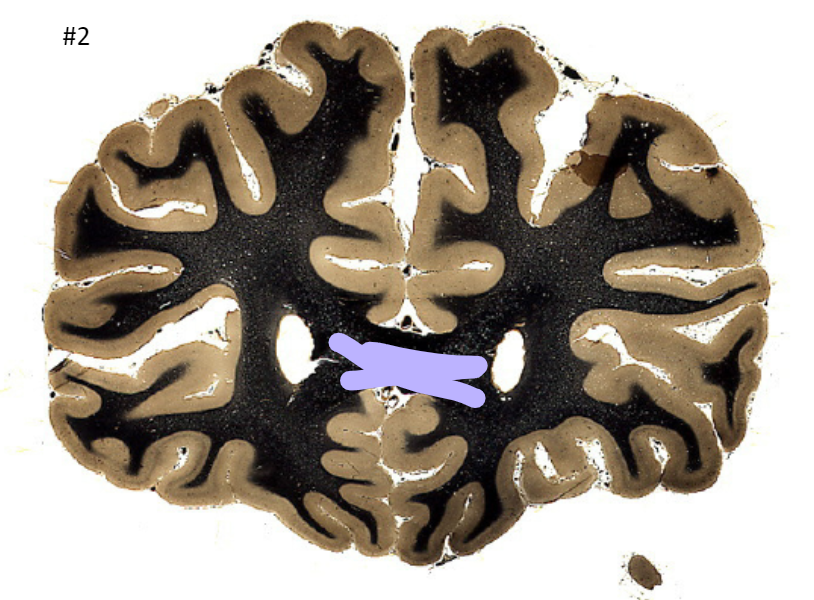

what is the circled area (#2)?

the corpus callosum

the lateral ventricle